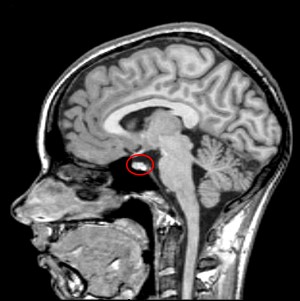

pituitary